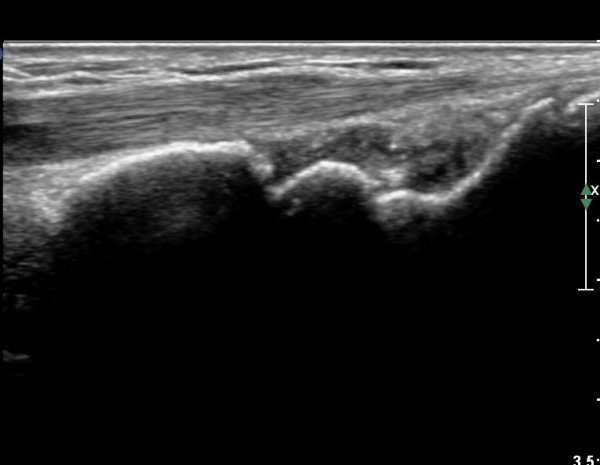

¼Õ¸ñÀÇ Á¾´Ü¸é°Ë»ç¿¡¼­ ¼Õ¸ñ °üÀý³» ºÎÁ¾ÀÌ °üÂûµÊ(»çÁø 1).